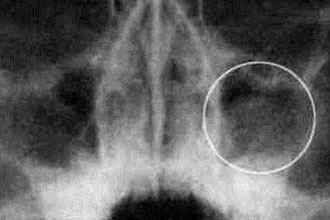

Магнитно-резонансная томография (МРТ) носовых пазух позволяет получить информацию о различных образованиях в тканях, не входящих в нормальную анатомию. В ходе исследования можно:

- Обнаружить кисты и опухоли.

- Разграничить опухолевую ткань от вторичных воспалительных процессов.

- Точно определить границы новообразования.

Основная задача МРТ – различение опухоли, реактивного выпота и отёка слизистой оболочки.

МРТ визуализирует мягкие ткани и позволяет оценить наличие воспалительного экссудата. В некоторых случаях требуется сочетание с компьютерной томографией, которая выявляет изменения в костных структурах. Результаты МРТ помогают врачу более эффективно планировать этапы хирургического вмешательства, оценивать возможные осложнения и прогнозировать исход операции.

Одним из ключевых преимуществ МРТ является более детальная визуализация новообразований по сравнению с рентгеновскими снимками и компьютерной томографией. Это связано с тем, что вокруг опухолей образуется зона реактивного воспаления, увеличивающая площадь патологических изменений на рентгенограммах и КТ. Однако при МРТ удаётся четко различить сигналы воспалённых тканей и опухолевых образований.